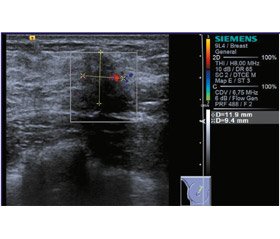

Найчастіше PASH проявляться утворенням, що пальпується аналогічно фіброаденомі [3, 7], але відомі випадки, коли вона була абсолютно асимптомною [4, 8] та виявлена лише за допомогою інструментальних методів. Відомі поодинокі випадки, коли були скарги на локальний біль та кров’янисті виділення з соска [9]. За результатами ультразвукового дослідження [10, 11], PASH проявляється гіпоехогенним утворенням з гетерогенною структурою (у 83 % випадків) та паралельною орієнтацією, нечітким контуром (62 %). За даними мамографії — високоінтенсивна тінь з нечітким контуром (тобто немає чітких рентгенологічних критеріїв для постановки діагнозу) [3] або локальна асиметрія [9]. За BIRADS зазвичай виставляли категорію 4 або 5. У 83 % випадків [11] для постановки діагнозу достатньо Core biopsy. Середній розмір утворень становив 4,2 см (від 0,8 до 11 см) [3]. Диференціювати необхідно з фіброаденомою, філоїдною пухлиною, гамартомою, ангіосаркомою, локальним фіброзом та низькодиференційованою ангіо–саркомою [12].

З анамнезу відомо, що гормональні контрацептиви не приймала, травми та хронічні захворювання заперечує, спадковий анамнез не обтяжено. За результатами об’єктивного огляду в правій молочній залозі виявлено щільне утворення розміром 2 см, безболісне, помірно рухоме, регіональні лімфатичні вузли мають фізіологічні властивості. За результатами ультразвукового дослідження (УЗД) в обох молочних залозах (рис. 1) виявлені гіпоехогенні утворення з нечіткими, нерівними контурами, посиленим перинодальним кровотоком, вертикальною орієнтацією щодо шкіри. За даними еластографії — мають високу щільність з характерними для гідрофільних включень мозаїчними зонами та ознаки перифокальної інфільтрації, виставлена категорія US-BIRADS 4C. У диференційно-діагностичному ряду розглянуті: карцинома, локальний аденоз, радіальний рубець, філоїдна пухлина. Виконано Core biopsy обох утворень голкою 14-10G, отримані стовпчики сіро-жовтого кольору відправили на гістологічне дослідження. Мікроскопічний опис препарату: матеріал представлений тільки фіброзною та жировою тканиною, визначаються численні щілиноподібні порожнини, що місцями анастомозують між собою, щілини вистелені міофібробластами, які імітують ендотеліальні клітини. В одному препараті визначається один проток, який вистелений двошаровим епітелієм без ознак атипії. Естроген-рецептор (DACO, клон EP1) — негативна реакція. Прогестерон-рецептор (DACO, клон PgR 636) — позитивна реакція у 90 % клітин протокового епітелію високої інтенсивності.